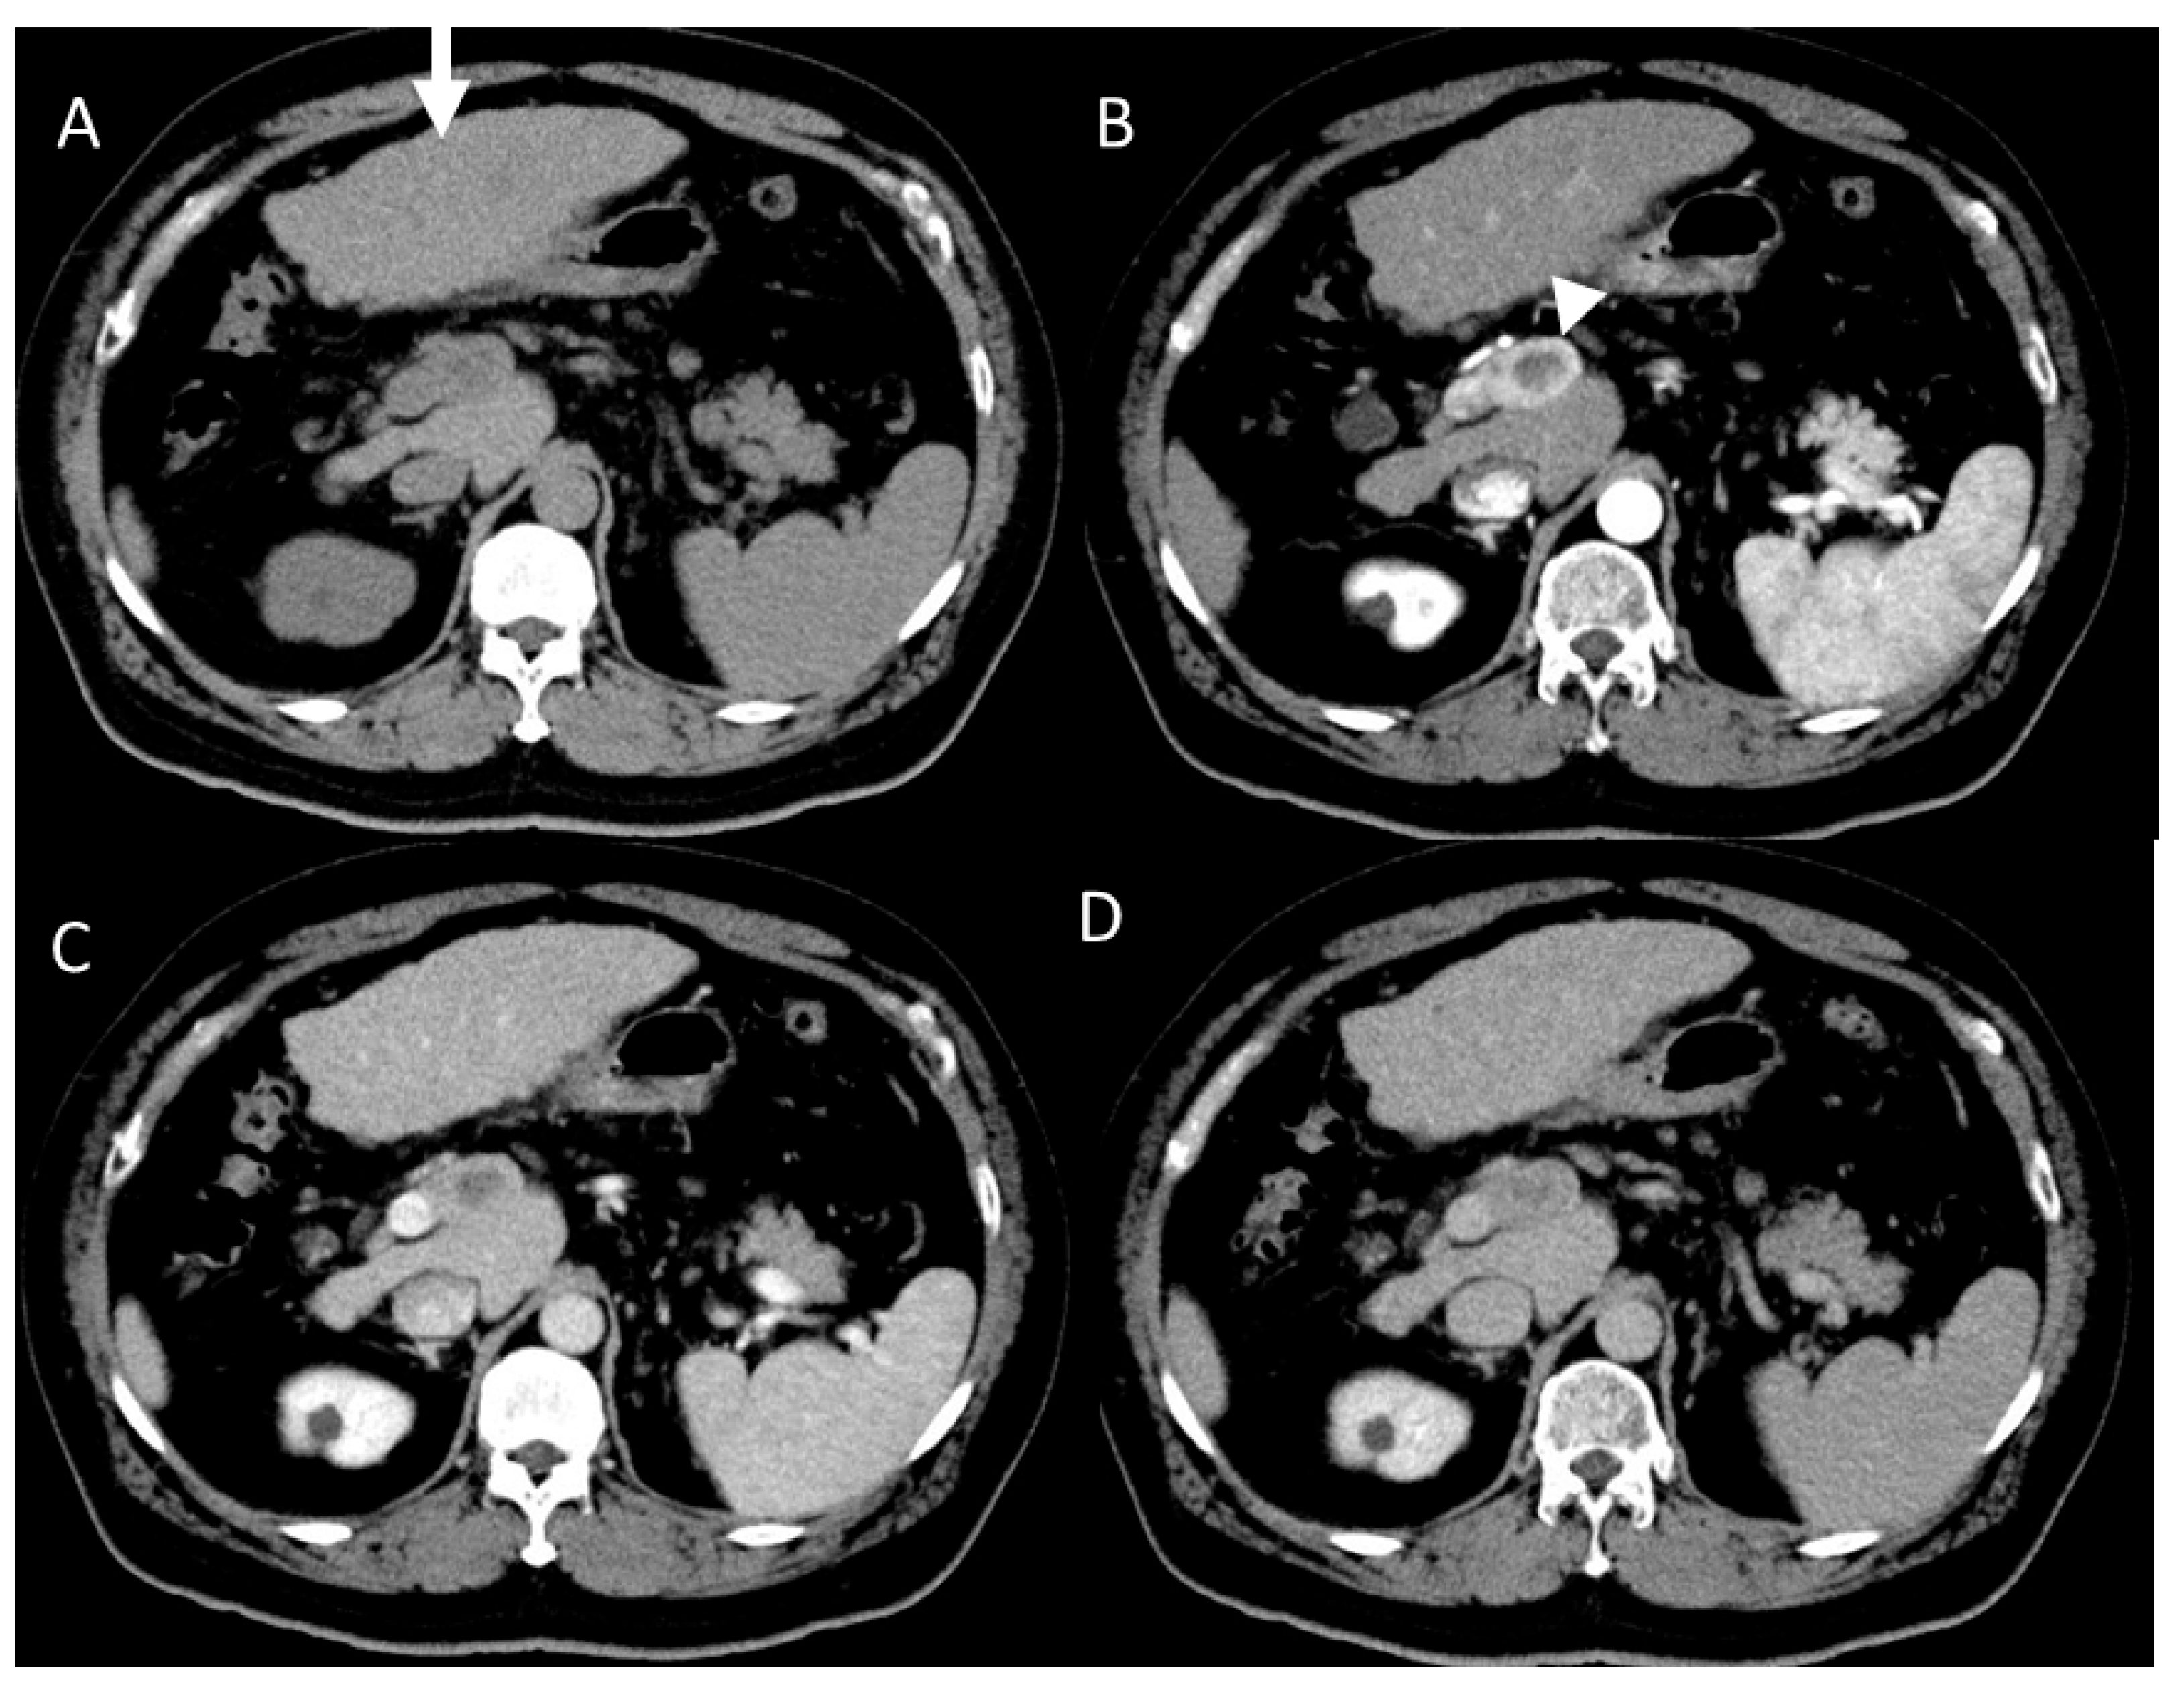

4.4. Moderately Differentiated Hepatocellular Carcinoma (Moderately HCC)

4.5. Poorly Differentiated Hepatocellular Carcinoma (Poorly HCC)